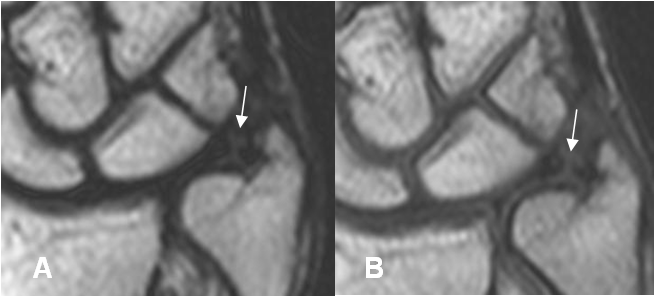

Fig 79 A. Ruptura del complejo del FCT.

A: RM coronal en T2 y B: RM coronal en T1. Solución de continuidad del cartílago, a nivel central por lesión tipo 1A.

Fig 79 B. Ruptura del complejo del FCT.

A: RM coronal en T1. Alteración en la señal del FCT, sobre su inserción ulnar.

B: RM coronal en GE. Solución de continuidad en la inserción ulnar del FCT, por ruptura tipo 1B. Existe líquido en la articulación radioulnar distal. (Flecha gruesa).